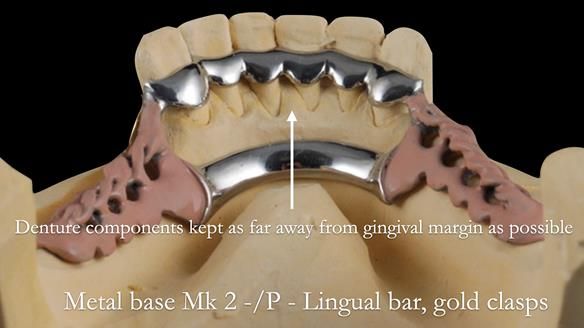

This newsletter describes the full protocol workflow of a complete upper denture and a lower partial denture for Jo.

- The forces placed on the teeth are large (bruxism). This will make the dentures proposed in the treatment plan below wear, chip and break more quickly. Therefore, the final dentures will require metal reinforcement to make them as robust as possible.

The clinical situation and treatment process is shown in detail below. I provided the clinical work. Rowan Garstang provided the technical work. This treatment took 25 visits over a period of 12 months.